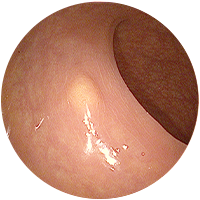

대장내시경 검사로 진단가능한 질환

-

1

선종